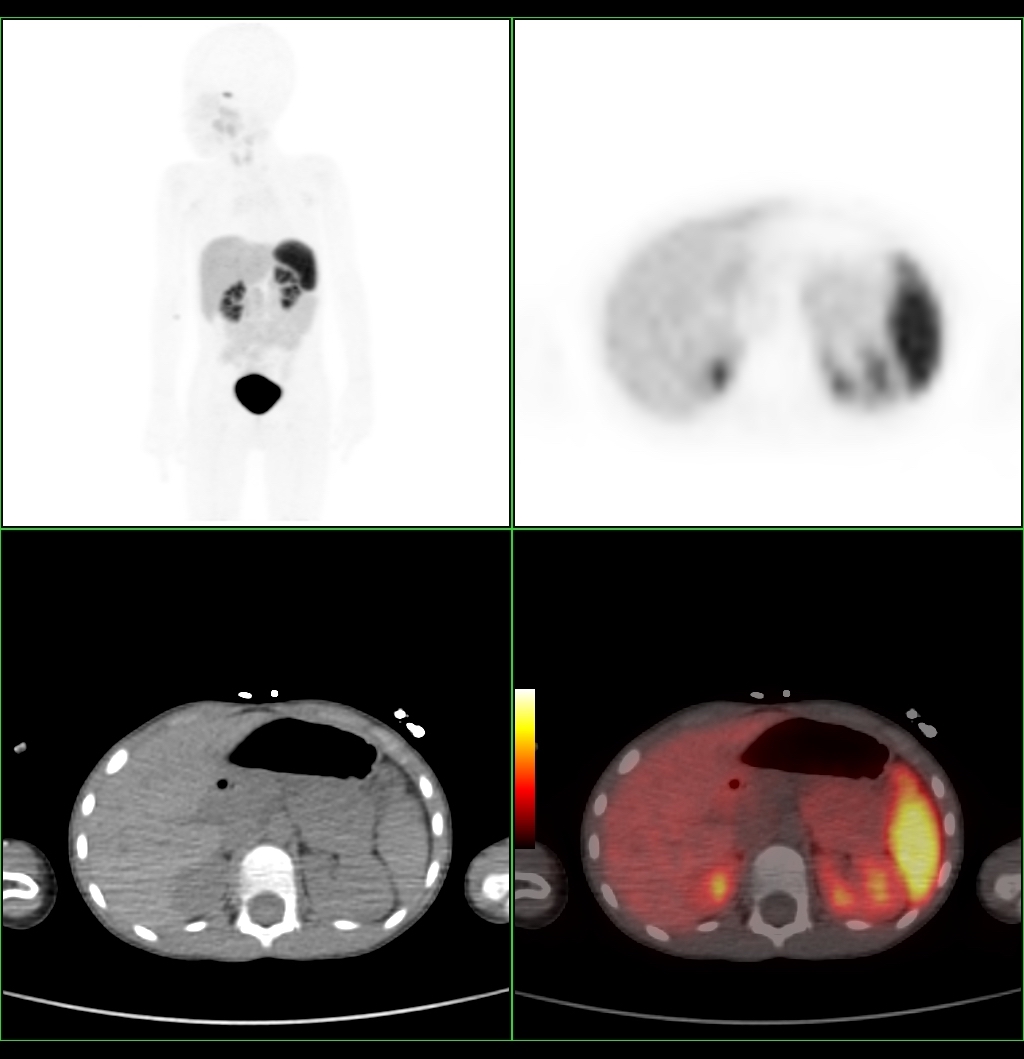

PET/KT tyrimas, pasitelkiant specialių radiofarmacinį preparatą, leidžia gydytojams aiškiai pamatyti kasos beta ląstelių padidėjimą ir nustatyti, ar insulino pertekliaus priežastis – vienas židinys ar difuzinis pažeidimas. „Šis metodas ypatingai svarbus sprendžiant dėl chirurginio gydymo – jeigu liga židininė, galime atlikti minimaliai invazinę operaciją ir pašalinti tik pažeistą kasos dalį, taip išsaugant sveiką audinį“, – pažymi Paulius Jaruševičius, Kauno klinikų Radiologijos klinikos gydytojas radiologas.

Pirmasis Lietuvoje tokio pobūdžio tyrimas buvo atliktas berniukui, kuriam nuo kūdikystės diagnozuotas įgimtas hiperinsulinizmas. Nors gydymas buvo taikomas nuo ankstyvo amžiaus, hipoglikemijos epizodai kartojosi. Genetiniai tyrimai parodė, kad vaikas yra ABCD8 geno patogeninio varianto nešiotojas – tokiais atvejais liga paprastai nepasireiškia, todėl reikėjo papildomo tyrimo. Atliktas PET/KT tyrimas padėjo gydytojams sudaryti individualizuotą gydymo planą ir suplanuoti tolesnę berniuko priežiūrą.